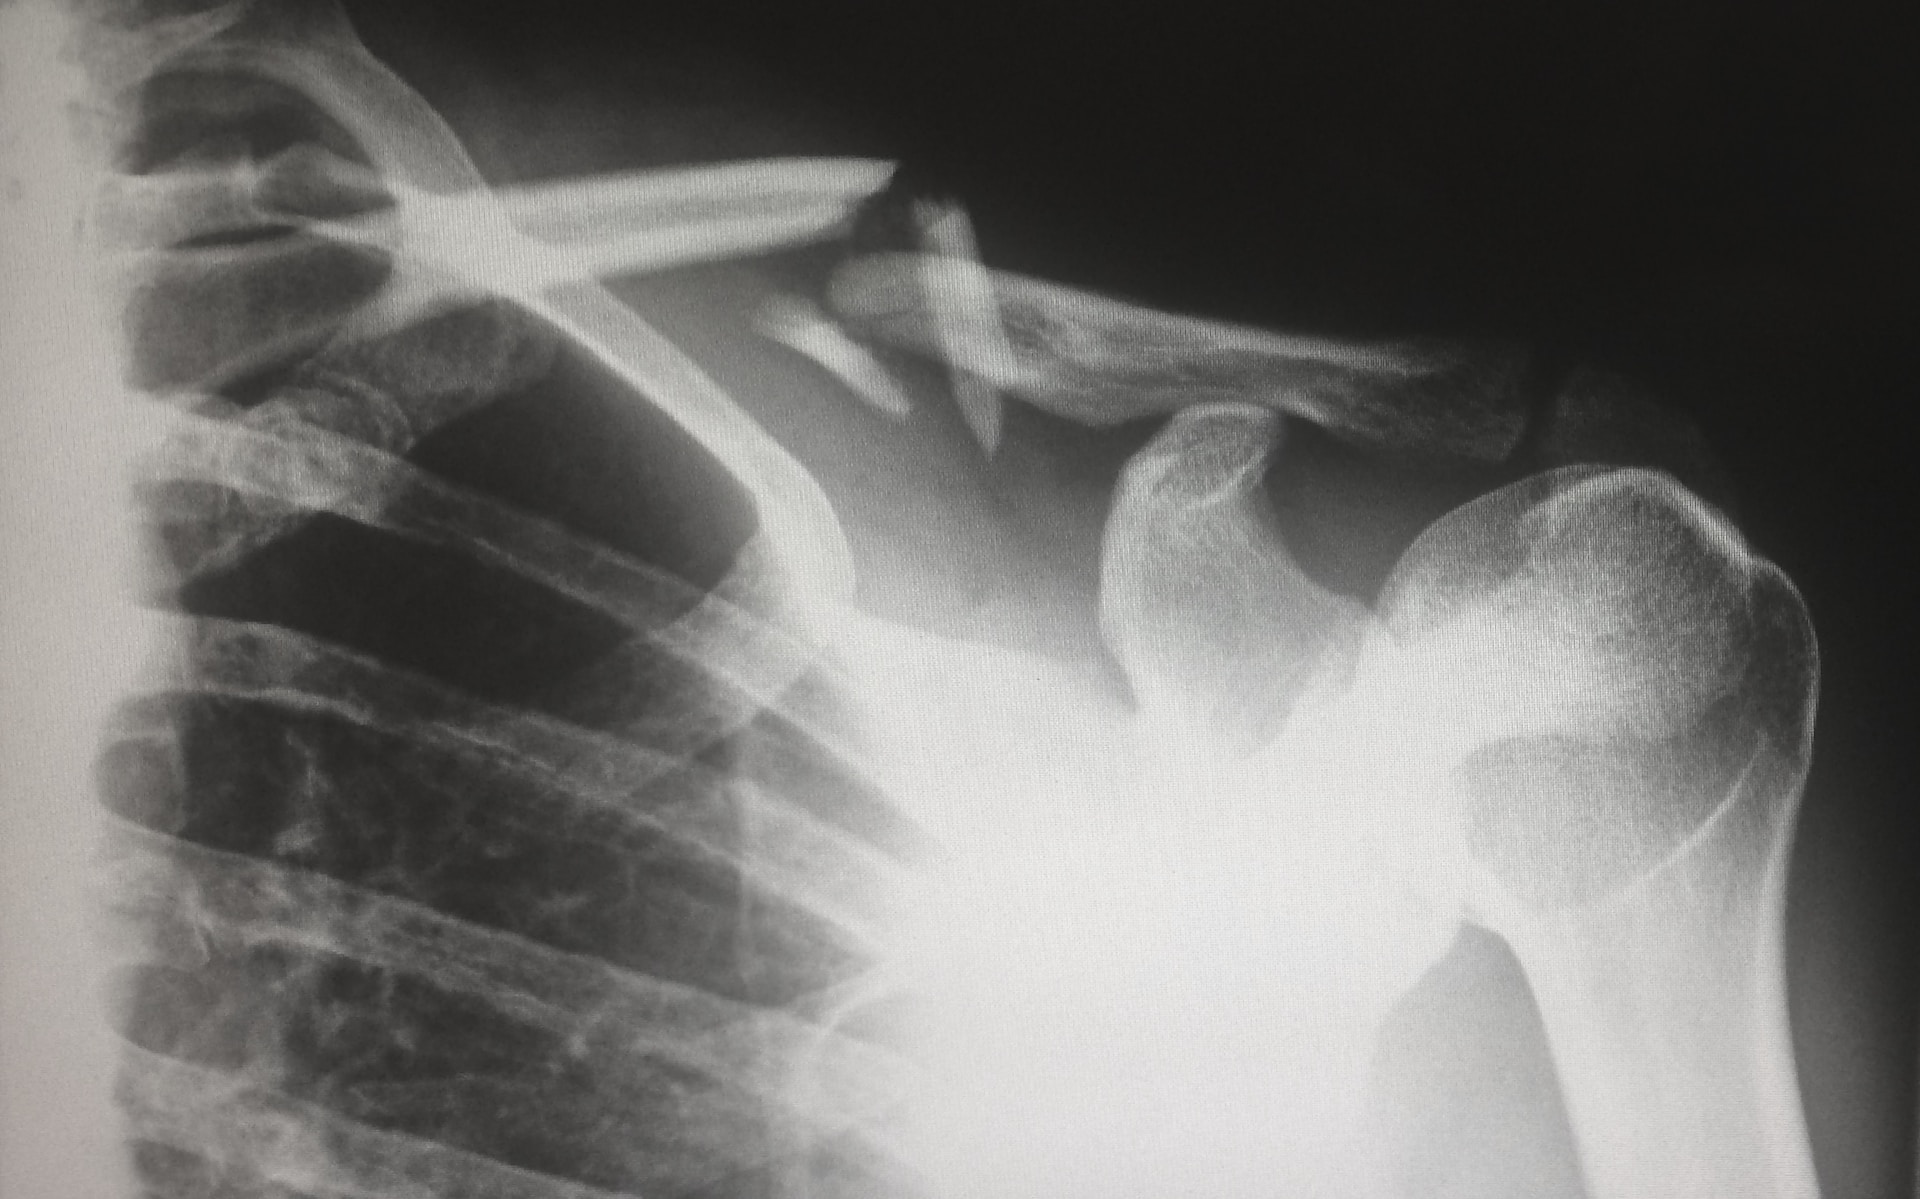

골다공증은 뼈의 밀도가 감소하여 뼈가 취약해지는 상태를 나타내며, 골절의 위험이 증가하며 이는 특히 골다공증으로 올 수 있는 골절 중에서 골밀도 검사를 통해 조기에 발견할 수 있는 경추와 대퇴부 골절이 중요합니다. 이러한 골절은 일상 생활에서 발생할 수 있으며, 더 나아가 심각한 건강 문제로 이어질 수 있습니다.

골다공증은 주로 골밀도 측정을 통해 진단됩니다. 이는 X선과 같은 방사선 검사로 측정되며, 특히 이중 에너지 X선 흡수측정(DEXA)이라고 불리는 방법이 일반적으로 사용됩니다.